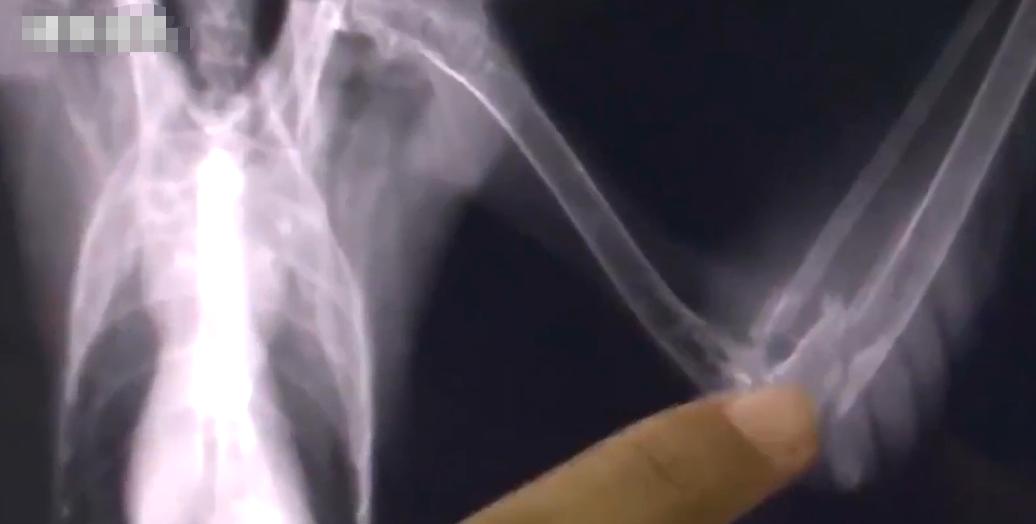

闫大哥抽空插话赶忙问起怪鸟病情,工作人员对怪鸟进行简单的检查,并没有发现怪鸟哪里有明显伤痕,只好带回林业局借助相关设备进行检查,一番检查下来发现这隼脚趾有轻微擦伤,不吃东西是因为得了抑郁症,并且患有肠胃炎,翅膀也轻微骨折,其他还好说,就这肠胃炎让工作人员很是苦恼,鸟类若是换上严重肠胃炎,不仅影响食欲,还无法正常飞行,最后只能郁郁而终。